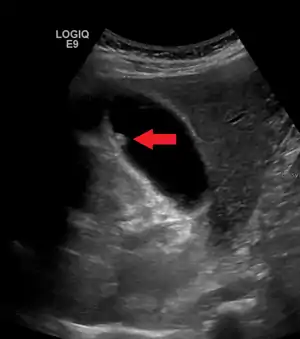

| A polyp in the gall bladder as seen on ultrasound |

Diagnosis is typically by ultrasound or CT imaging.